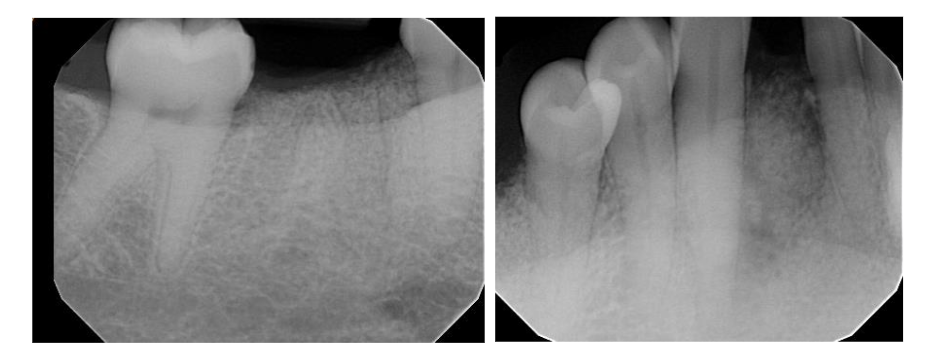

Figure 2. Preoperative intraoral periapical radiograph taken to show bony contour from teeth #23 to tooth #31. A large low dense bone noted around #26 that extended from alveolar ridge to apex of the teeth #26 and 27. In addition, radiograph showed an endodontic lesion at the apex of #30.